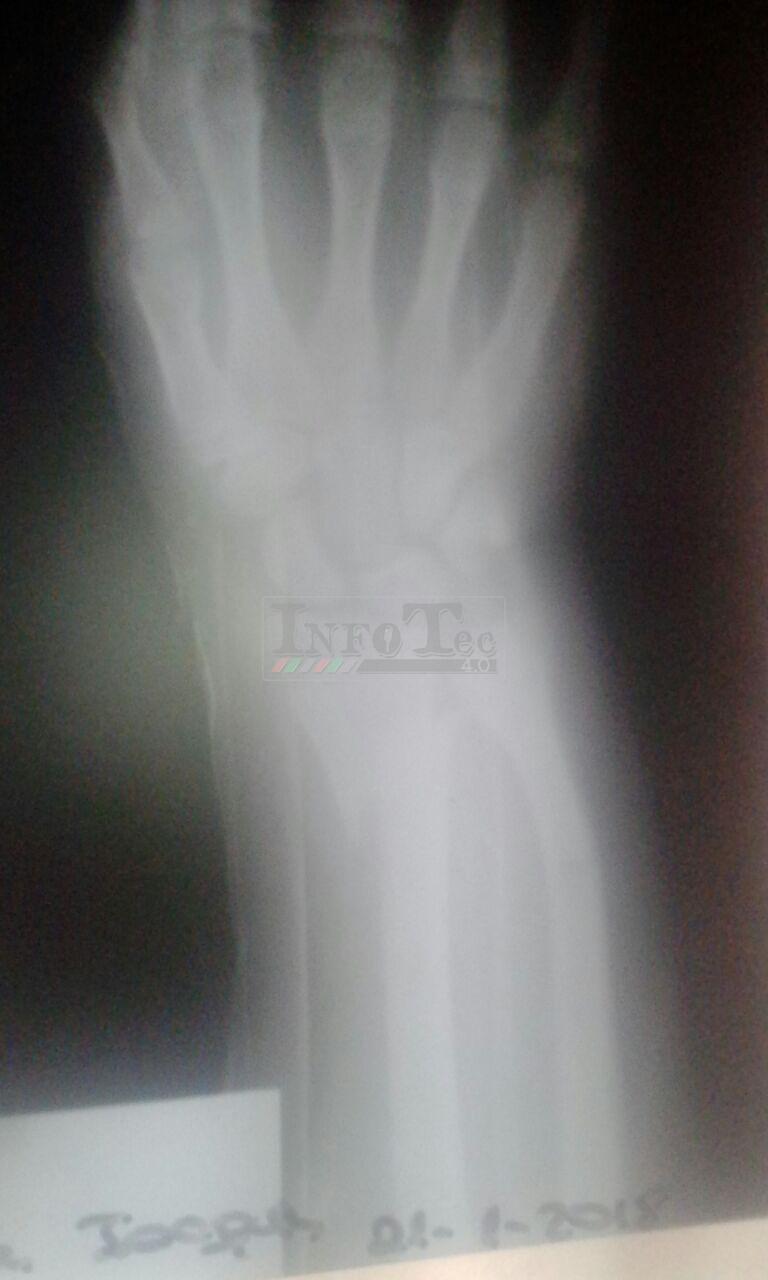

Tras ser atendido el traumatólogo constató que el pequeño presenta fractura de Radio y Cúbito en su brazo derecho con desplazamiento, además de múltiples escoriaciones dado que al caer golpeó contra uno de los puentes de material que hay en el lugar para trasponer el canal y acceder a las viviendas del sector.

Se le practicó un yeso provisorio y seguramente durante el día de mañana sería trasladado a Pico para ser evaluado por especialistas siendo probable la necesidad de una intervención quirúrgica - afirmó su mamá.-